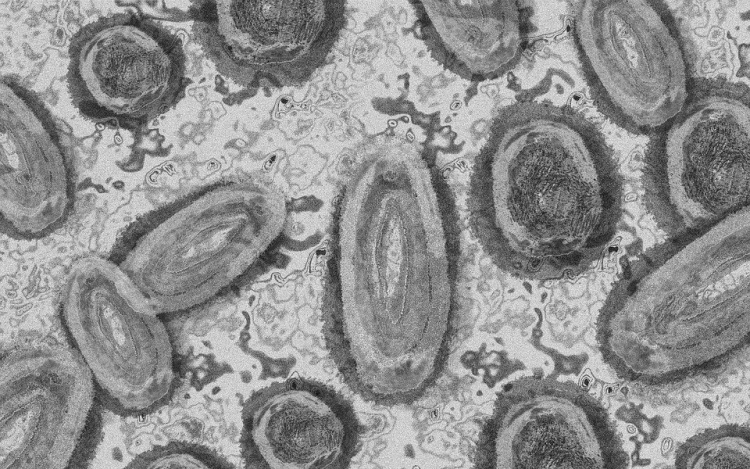

Megfertőződött majomhimlővel egy négyéves kislány Németországban - jelentették kedden német hírportálok az országos közegészségügyi intézet (RKI) adatai alapján.

Németországban első alkalommal mutatták ki a kórokozót gyermek szervezetében.